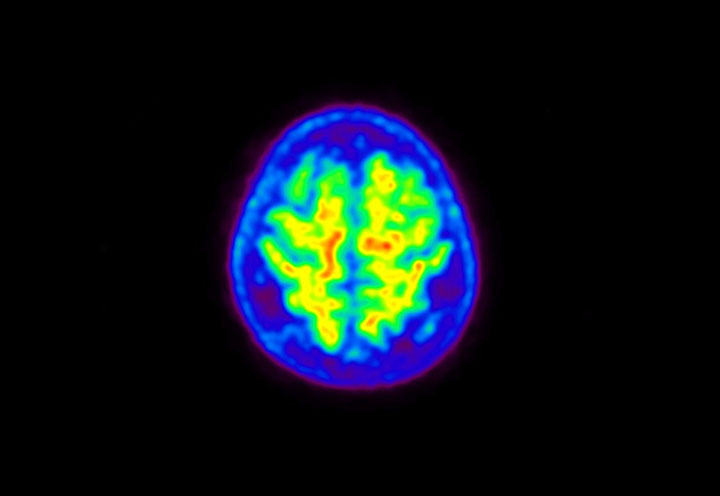

Head / Case5 : Amyloid

Axial

Courtesy : Kindai University Hospital

- Imaging protocol

- Injected dose: 4.27 MBq/kg, 18F-Flutemetamol

- Uptake time: 99 minutes

- Scan time: 20 minutes